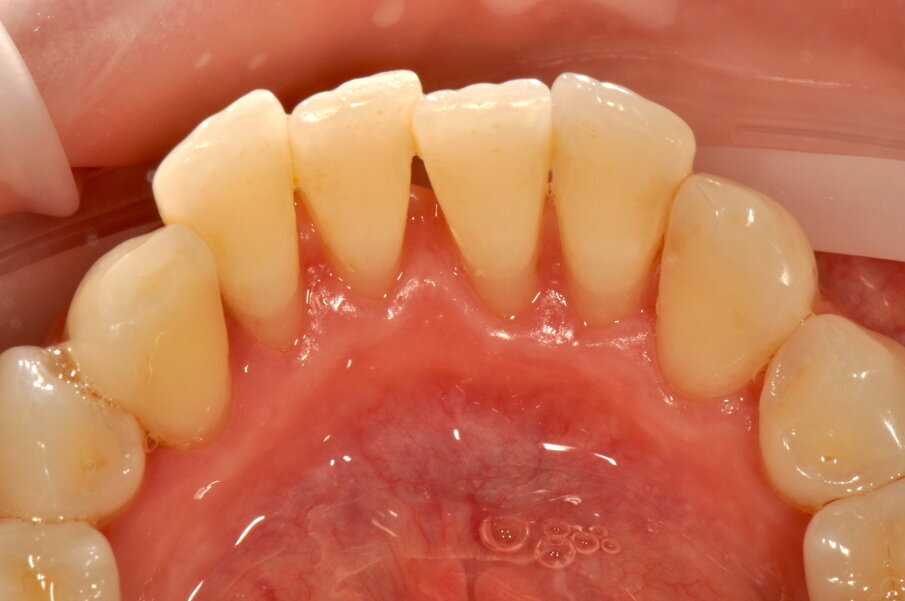

Figg. 1a-1c - Applicazione del rilevatore di placca che verrà usato come guida durante la terapia, nel versante vestibolare (1a), palatale (1b) e linguale (1c). Si noti lo scarso livello di igiene orale domiciliare e l’assenza di utilizzo dei presidi interdentali.